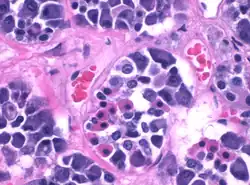

Adenohipófisis. Se observan capilares con glóbulos rojos.

Durante mucho tiempo se consideró a la adenohipófisis como similar a un mosaico aleatorio de células productoras de hormonas. El uso de imágenes 3D de toda la adenohipófisis, ha descubierto redes de células neuroendócrinas altamente organizadas e interdigitadas, con interacciones entre células del mismo tipo y de tipo diferente.

Otros componentes conforman el tejido de soporte (estroma) como las células gliales, las células foliculoestelatas y un lecho capilar abundante.[4]